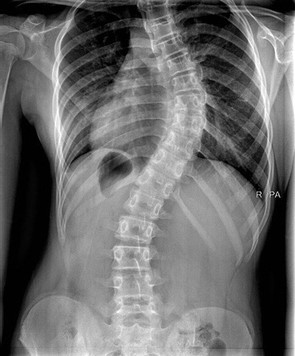

Corset orthopédique

Le corset orthopédique est un appareillage réalisé sur mesure.

En agissant sur la colonne vertébrale (dorsale/lombaire) son objectif est :

• De maintenir le rachis dans une position bien définie

• De corriger ou prévenir l’aggravation d’une déviation de la colonne vertébrale

• D’immobiliser de façon temporaire ou définitive le segment du rachis

• De Limiter l’effondrement du rachis

Les corsets correcteurs et de maintien:

• Chêneau, CTM, Milwaukee, Boston, ...

• Corset lombaire délordosant, ...